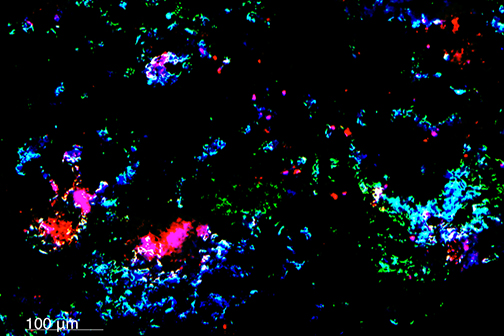

A study led by Nicolas Bazan, MD, PhD, Director of the LSU Health New Orleans Neuroscience Center, pinpointed which cells within specific areas of the brain are involved in post-stroke response and found that the delivery of precursors of Elovanoids, a class of molecules that synchronize cell-to-cell communication and neuroinflammation/immune activity in response to injury, improved neurological deficit in an experimental model of ischemic stroke. More

LSU Health New Orleans Researchers Discover a Key Failure in AMD that May Lead to Progression & Vision Loss

Research led by Nicolas Bazan, MD, PhD, Boyd Professor, Ernest C. and Yvette C. Villere Chair for the Study of Retinal Degeneration, and Director of the Neuroscience Center of Excellence at LSU Health New Orleans School of Medicine, suggests that age-related macular degeneration (AMD) decreases an essential fatty acid, preventing the formation of a class of protective molecules and reducing repair potential. The discovery may also open new therapeutic avenues for AMD. More

LSU Health New Orleans Researchers Discover Potential New Rx Strategy for Ischemic Stroke

A study conducted by scientists at LSU Health New Orleans’ Neuroscience Center of Excellence reports that the additive neuroprotection of a combination of two omega-3 fatty acid-derived signaling molecules is more effective in protecting brain cells and increasing recovery from stroke in an experimental model than a single drug. More

LSU Health New Orleans Develops New Human Cell Line to Study Blinding Eye Disorders

Under the direction of Boyd Professor Nicolas Bazan, MD, PhD, scientists at LSU Health New Orleans Neuroscience Center of Excellence have developed a new, experimental human cell line from retinal pigment epithelial cells. Called ABC, these cells so closely resemble and retain the properties of native retinal pigment epithelial (RPE) cells, the research team has shown that they are a reliable cell system to study retinal degenerative diseases. More

LSU Health Contributes to Research Suggesting Late-Onset Retinal Degeneration Mechanism & Potential Rx

A study led by the National Eye Institute (NEI) that included five researchers from the Bazan Lab at the LSU Health New Orleans Neuroscience Center of Excellence has discovered how late-onset retinal degeneration can develop and a surprising potential therapeutic -- metformin. The results are published online in Communications Biology, a Nature journal. More

A study led by Nicolas Bazan, MD, PhD, Boyd Professor and Director of LSU Health New Orleans Neuroscience Center of Excellence, reports that in an experimental model of glioblastoma multiforme (GBM), a combination of approved and novel therapeutics improved survival and reduced tumor volume and growth. More